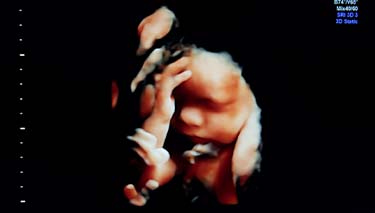

4D Ultrasound

4D or 4 dimensional scans build on the technology of 3D scans. The extra dimension is time, so that effectively 4D ultrasounds are moving images of your baby in real time. As your baby kicks, moves, frowns, grimaces, sucks their thumb, opens their eyes and moves their lips, you will be able to see these movements on the scan as they are actually happening.

3D Ultrasounds are also known as elective prenatal ultrasounds. They are not designed to replace the standard 2D procedure which is commonplace obstetric procedure. Instead they offer a more enhanced bonding experience with the unborn baby and are instigated by parents choosing to have them done, rather than a medical need. Some parents are very keen to see for themselves how their baby is growing and developing, and for this reason another name for the 4D ultrasound is a lifestyle scan.